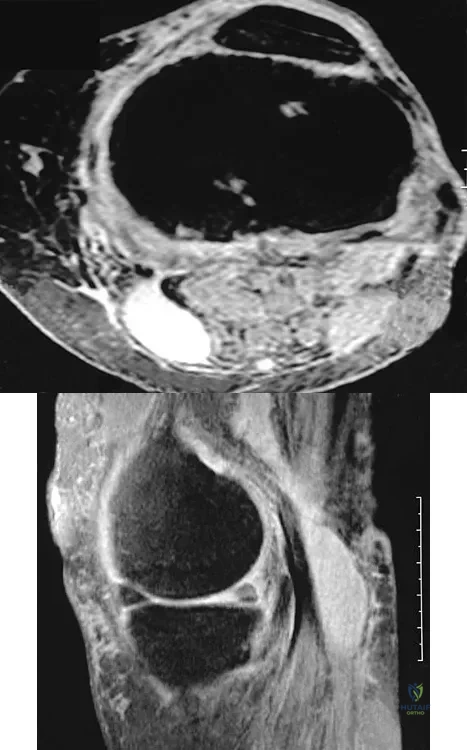

A 28-year-old man reports knee stiffness, swelling, and a constant ache that is worse with activity. Examination reveals an effusion, global tenderness, and warmth to the touch. Flexion is limited to 110 degrees. Figures 48a through 48d show sagittal T1-weighted, sagittal T2-weighted, axial T1-weighted fat-saturated gadolinium, and axial gradient echo MRI scans. Based on these findings, what is the most likely diagnosis?

Explanation